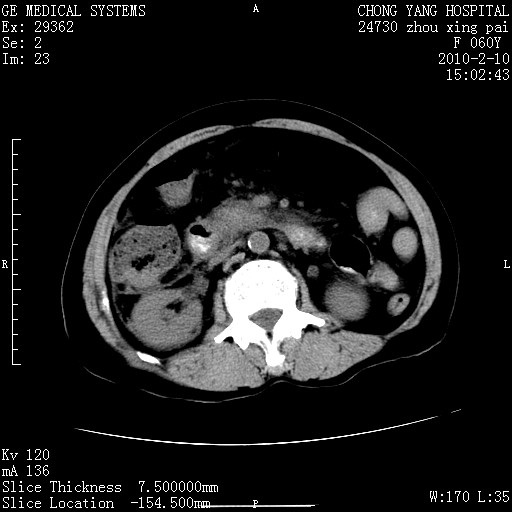

标题: CT24682:F60Y 腹痛 其它不详 [打印本页]

标题: CT24682:F60Y 腹痛 其它不详

胆总管末端梗阻!结石?肿瘤?建议增强!必要时行ercp!

胆总管末端梗阻!结石?胰腺影增粗,以胰腺头部为著,胰周看见渗出影,双侧胸腔积液,(胸膜反应)考虑胰腺炎。

1)胆总管末端梗阻,不排除结石所致可能。2)胰腺炎。3)慢性胆囊炎可能。4)左侧输尿管上段扩张。5)少量腹水。6)双侧少量胸腔积液,伴两下肺部分肺萎陷。

1)胆囊炎。2)胆源性胰腺炎。3)右肾周筋膜增厚,肾旁前间隙积液。4)左侧输尿管上段扩张。5)少量腹水。6)双侧少量胸腔积液,伴两下肺部分肺膨胀不全。

急性胰腺炎所致胆总管扩张!

1)胆总管末端梗阻。2)胰腺炎。3)慢性胆囊炎可能。4)左侧输尿管上段扩张。5)少量腹水。6)双侧少量胸腔积液,伴两下肺部分肺萎陷。